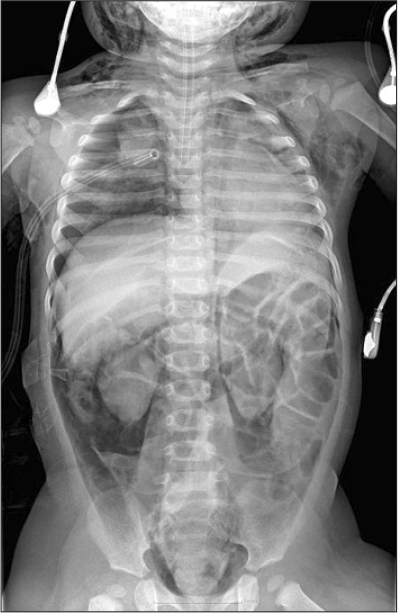

Chest x-ray showing bilateral pneumothorax with a flattened diaphragm... | Download Scientific ...

Chest x-ray showing bilateral pneumothorax with a flattened diaphragm... | Download Scientific ... from www.researchgate.net